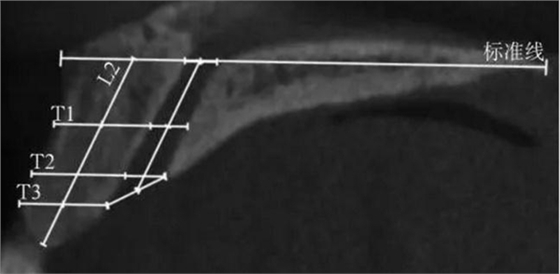

(1)正中矢狀面(圖1~3)。所使用的測量參數(shù)及其定義如下所述。鼻腭管高位直徑(S1):標準線交鼻腭管處的管徑;鼻腭管中位直徑(S2):鼻腭管長軸中點處的管徑;鼻腭管低位直徑(S3):管后壁腭側骨最低點至對應管前壁的水平管徑;切牙孔開口直徑(S4):管后壁腭側骨最低點至唇側骨低位厚度和管前壁交點的直線距離。唇側骨高位厚度(T1):S2平面處唇側骨板水平厚度;唇側骨中位厚度(T2):S3平面處唇側骨板水平厚度;唇側骨低位厚度(T3):唇側骨最凸處骨板水平厚度。鼻腭管長度(L1):S1與S4中點間的距離;唇側骨長度(L2):唇側骨下端最低點經(jīng)T1、T3中點至標準線的直線長度。鼻腭管傾斜角度(A1):L1和標準線的垂線所成角度;唇側骨傾斜角度(A2):L2和標準線的垂線所成角度。

T1:唇側骨高位厚度;

T2:唇側骨中位厚度;

T3:唇側骨低位厚度;L2:唇側骨長度。

圖 2 矢狀面唇側骨板測量方法

Fig 2 Measurements ofcorresponding buccal bone